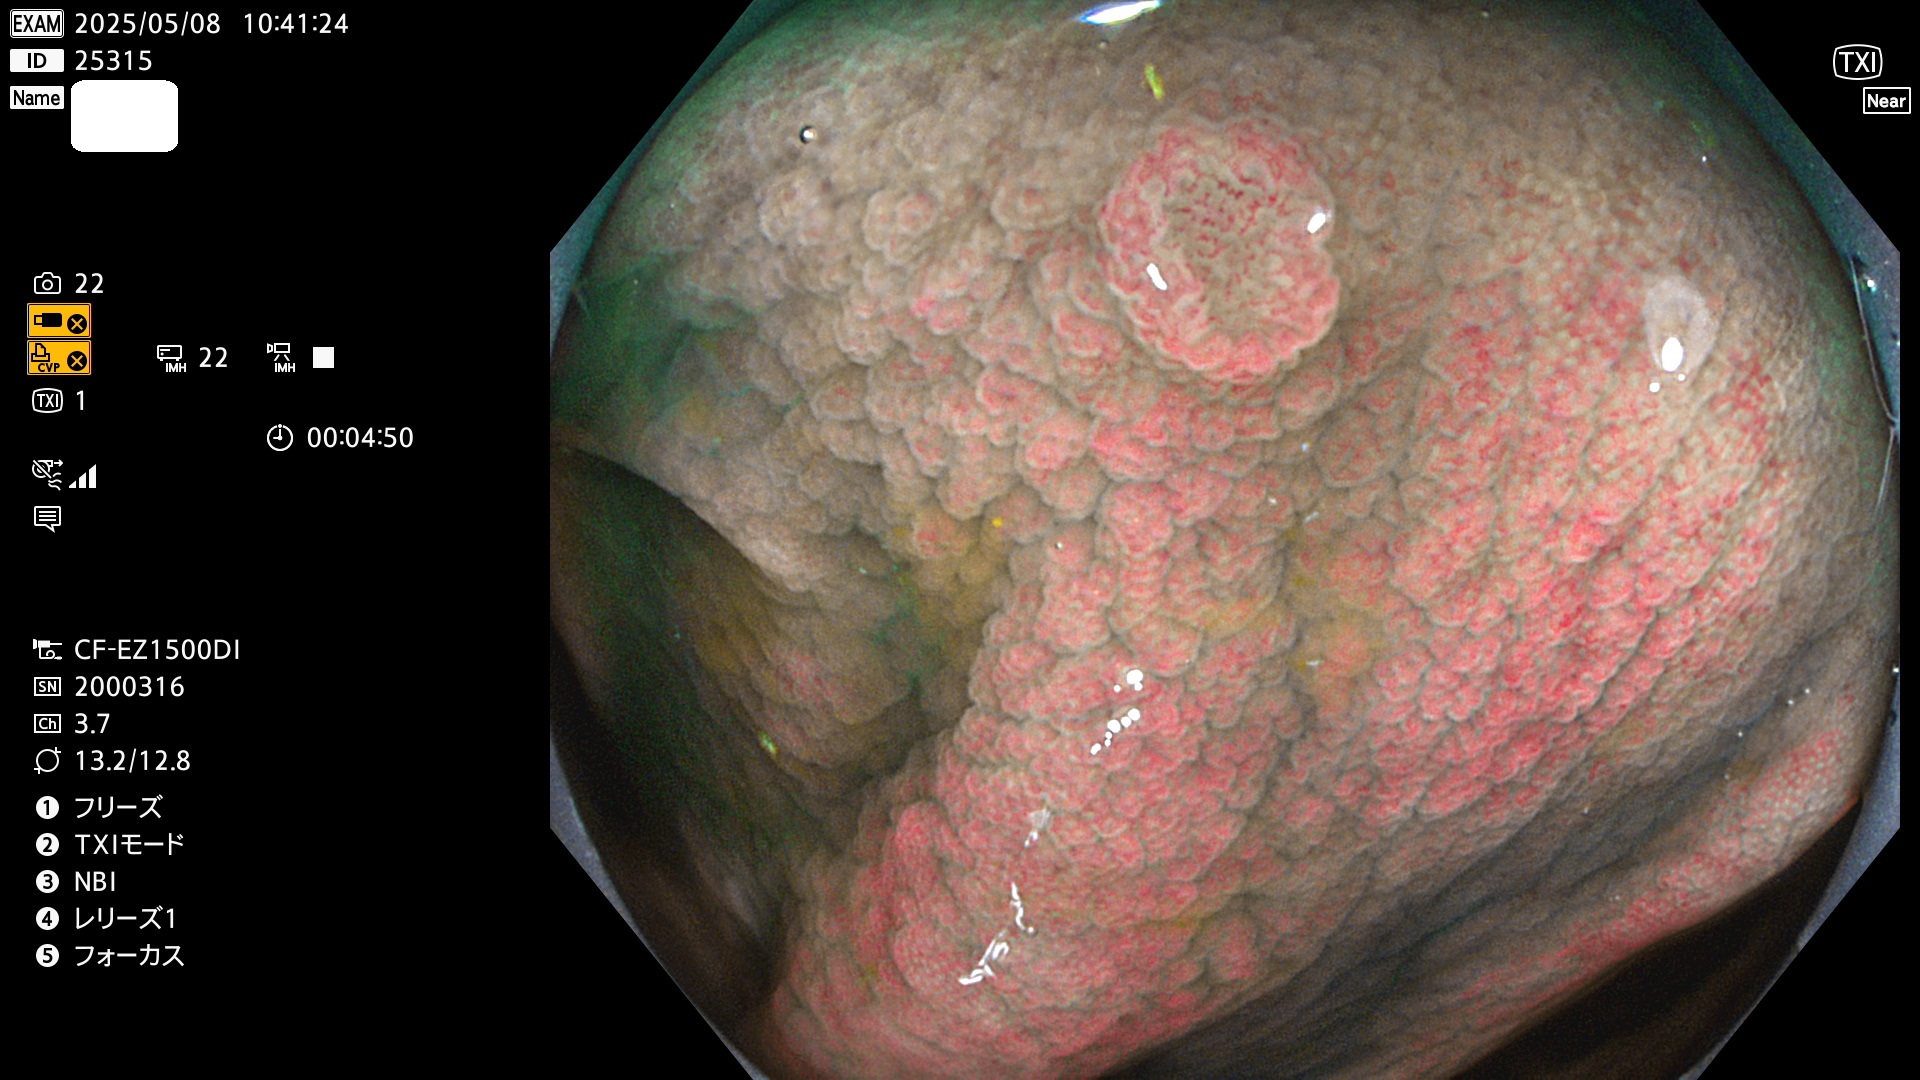

今週のUb、Uc型腺腫

完全に平坦な物をUb、陥凹している物をUcと呼びます。Ubは認識が困難で、Ucはびらん(炎症)と紛らわしいために見落とされやすく、「内視鏡後・大腸癌」の原因になります。

抽出の対象期間 2025年5月8日〜5月11日の4日間(48件の検査)14個 (14/48=29%)